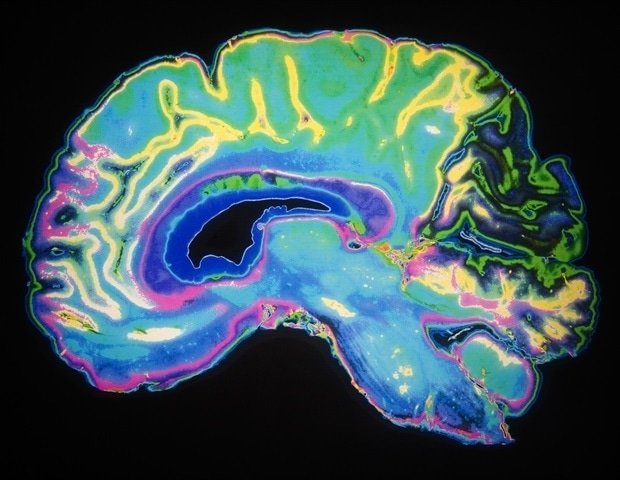

During intensive care after premature birth, babies may experience hypoxia, a lack of oxygen in their tissues and cells. Hypoxia is associated with poor brain health and lifelong memory loss, but the mechanisms are unclear. Researchers led by Art Riddle and Stephen Buck at Oregon Health and Science University discovered the contributing mechanism by creating a mouse model of mild hypoxia after preterm birth. “Historically, the field has focused on how hypoxia damages the brain’s white matter and destroys neurons,” Riddle said. “This study is the first to explore how mild hypoxia changes brain development during this neonatal period, without direct brain damage.”

As introduced in them, JNeurosci Mild hypoxia shortly after birth impairs learning and memory into adulthood, according to the paper, and researchers have discovered at least part of the mechanism for this effect. It is a change in communication between neurons in the hippocampus. The researchers investigated the molecular mechanisms and found that hypoxia after preterm birth affects protein channels involved in communication between neurons and memory that develop in the hippocampus during adolescence. They also identified a second protein involved in the effects of hypoxia on channel function. When the researchers targeted this second protein in adult mice, the channel’s function was restored. Riddle added: “When we looked at surrounding brain regions, we also found that this protein was altered by mild hypoxia, suggesting that other brain regions may also be susceptible to hypoxia.” In future studies, the researchers plan to assess how hypoxia affects these areas.